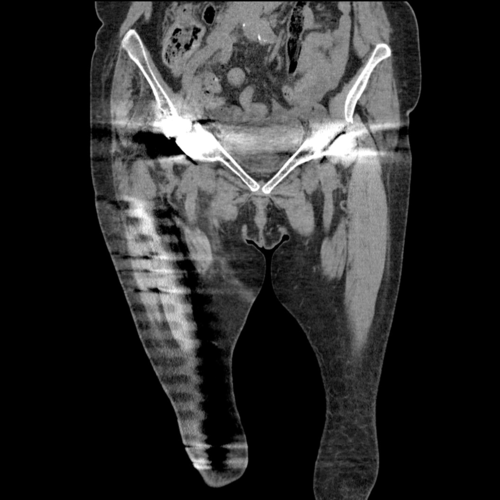

A pre-operative scannogram demonstrating the dislocation of the right implant from the constrained acetabular liner

Pre-operative cross sectional imaging demonstrates the extent of the intrapelvic migration